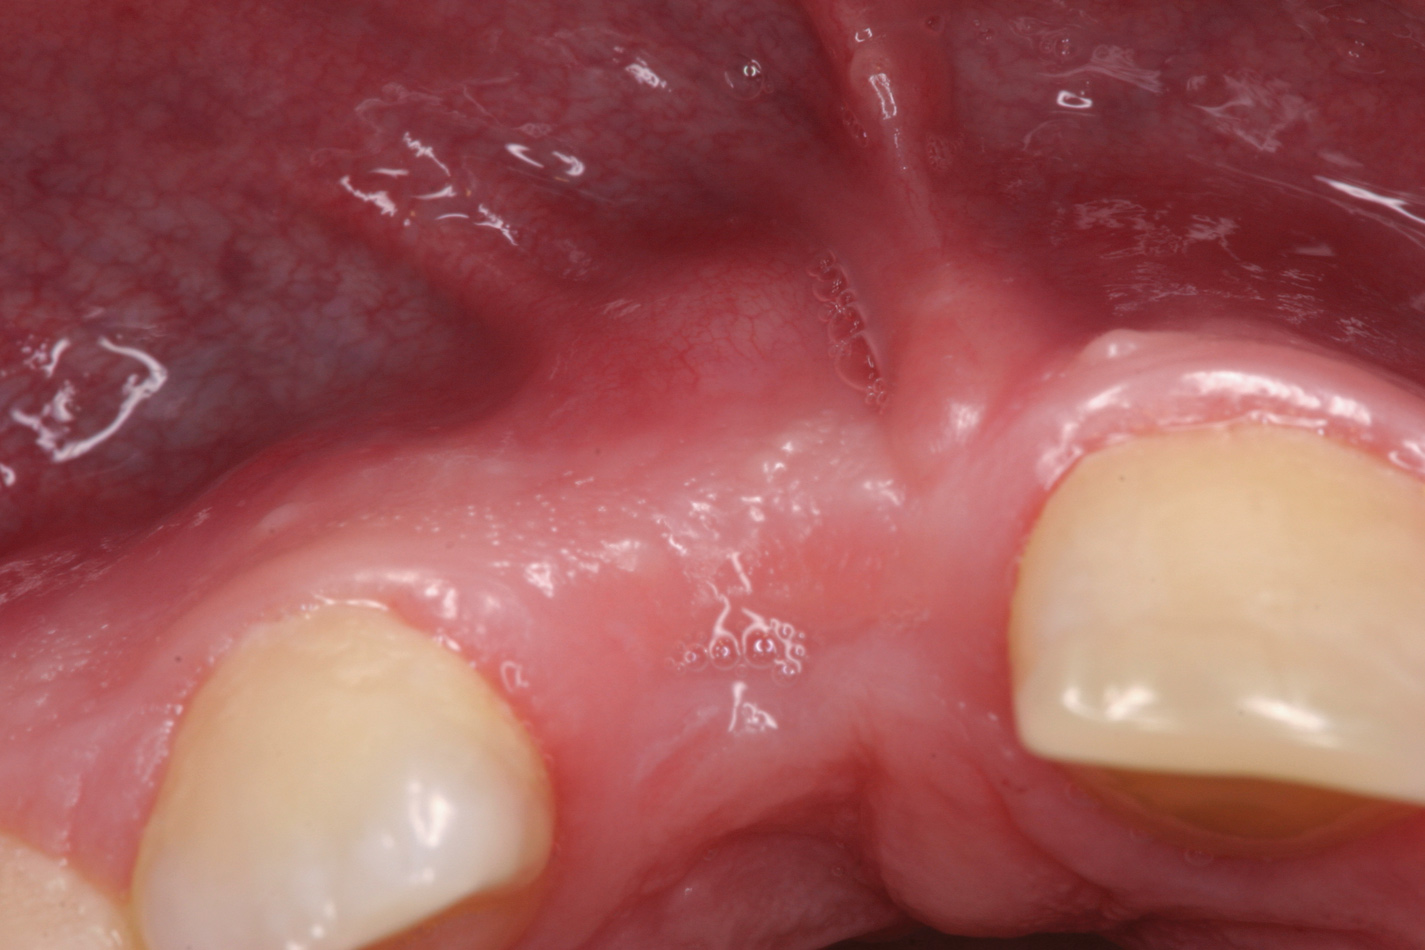

Fig 4. Age 10. Occlusal view of maxillary ridge.

Figure 4

From age 8 to age 19, midfacial skeletal growth occurs. Without a tooth, the alveolar ridge does not fully develop vertically and the ridge loses about one-third of its labial width after the tooth is lost.16,17 In case 1, clinical photographs and radiographs were routinely obtained. When compared, photographs taken at different ages appear very similar in both the facial (Figure 5 and Figure 8) and occlusal views. The levels of the tissue in the edentulous area relative to the incisal edges of the lower anteriors were quite comparable, as were the levels of the papillae on either side of the site. The width of the alveolar ridge in the extraction sites looked much the same from occlusal views (Figure 4, Figure 6, and Figure 9).

Allowing for differences in radiographic angulation, the apices of the retained roots remained in a similar position relative to the apices of the adjacent teeth as did the coronal edges of the root relative to the CEJs of those teeth (Figure 3, Figure 7, and Figure 10). It appears that the retained roots preserved the developing ridge associated with them in a manner similar to the developing ridge next to the injury site during the child's 11 years of growth. The final result was an intact alveolar ridge with an adequate labial plate at the proper level for an implant (Figure 11).